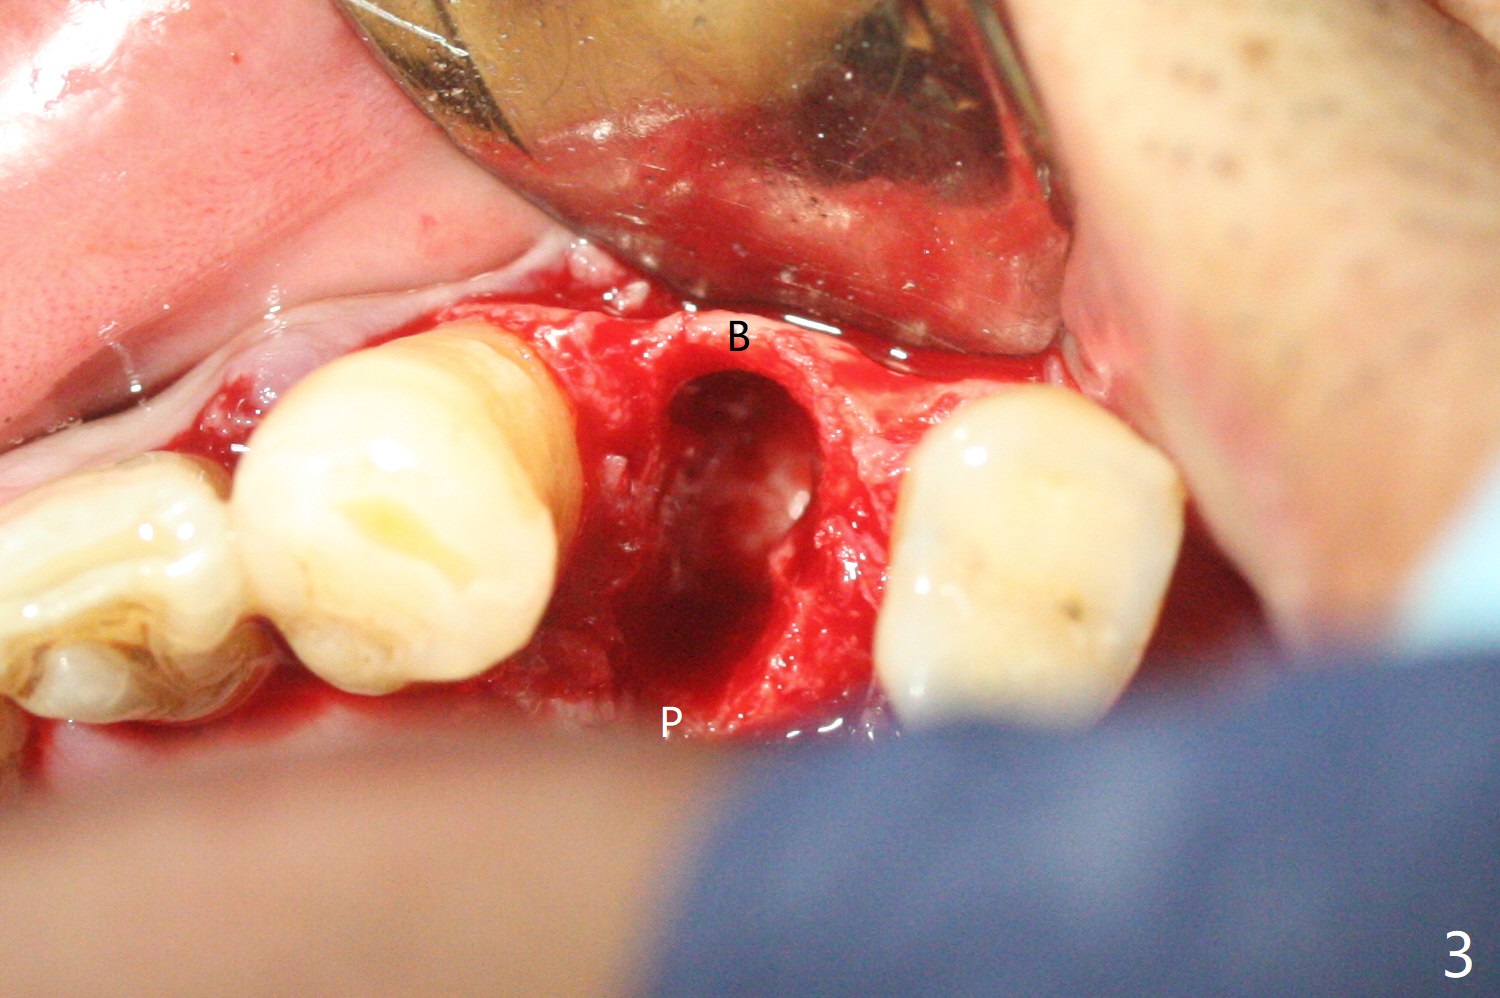

58岁男,吸烟,要求拔除断裂左上4(图一,二),邻牙(5)骨质吸收严重(图一,四),右上4,5拔除后骨质吸收(图一),所以左上4拔除(图三)位点保留(图四:人工骨,图五:GEM Cap)重要,尽管他准备做假牙。